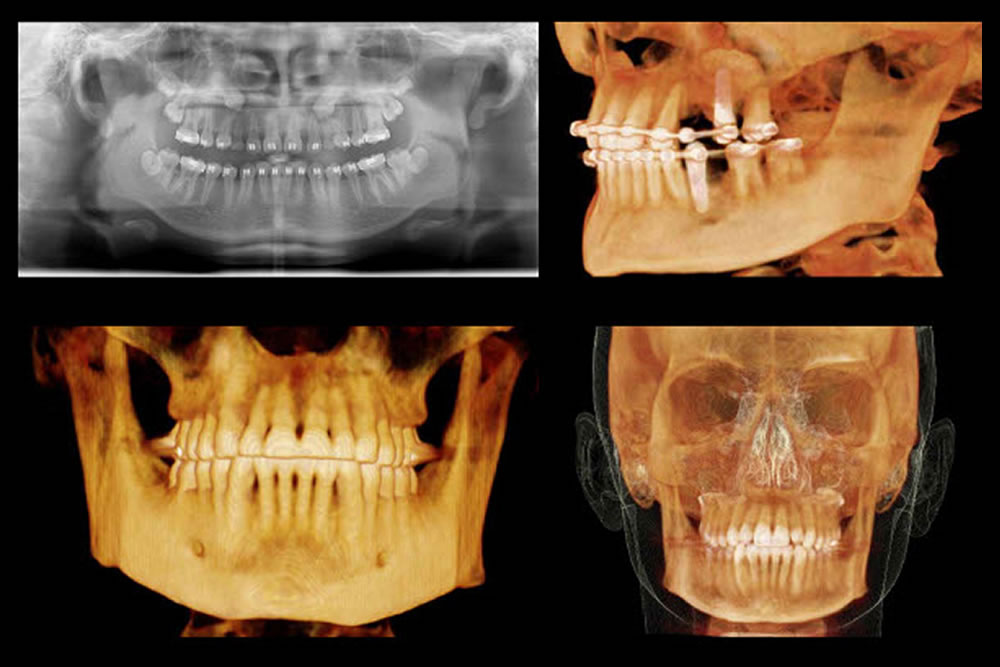

事前にCTによる精密検査を実施

インプラント治療をトラブルなく行うためには、事前の検査が重要となります。当院ではCTによる精密検査を実施し、顎骨の状態や神経の位置を確認し、適切な治療計画を立案いたします。

サージカルガイドの使用

インプラント手術の際は、CTの精密検査データを用いたシミュレーションの結果を基に作成したサージカルガイドという器具を使用します。サージカルガイドは、インプラントの埋入位置、埋入角度、ドリルの最終到達点などが反映されているため、手術時の人為的なミスを防ぎ、シミュレーション通りの位置へインプラントを埋入することができます。